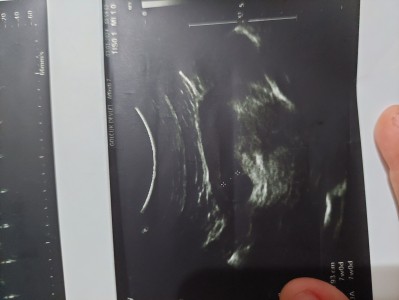

Merabalar 7 haftalık bu görüntüde duydum kalp atışını ama kese sanki noktanin oldugu yere gore cok genis buyuk gibi normal mi bu sekilde olması

Gebelik haftası 8.2